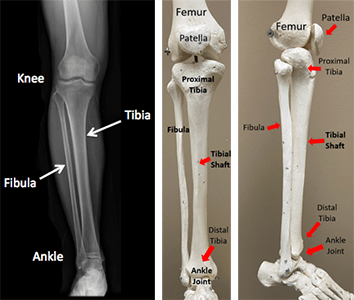

Another bone, the fibula, is found on the outside of the leg. It is not directly part of the knee joint, but many of the important structures of the knee attach to the fibula.

2. Tibia (Shin Bone)

The tibia is another long bone that is found between the knee and the foot. The top surface of the tibia is essentially flat and is known as the tibial plateau. The femur sits on this flat area.